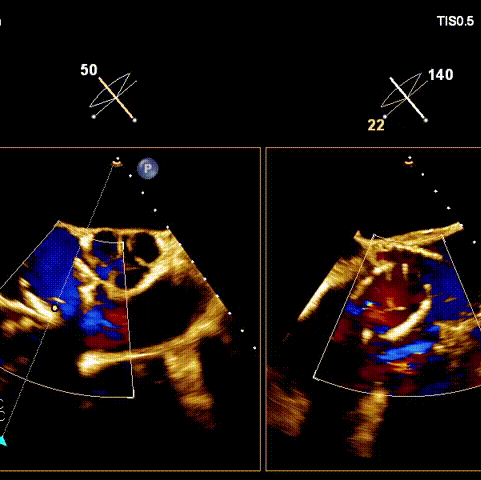

術(shù)前超聲

接受手術(shù)的為一名80歲男性,因“心悸2年,氣喘伴下肢水腫半年”入院。超聲心動(dòng)提示“極重度三尖瓣反流,右房及右室明顯擴(kuò)大,右心收縮功能輕度減低,左心收縮功能正常,肺動(dòng)脈壓力正常”。患者同時(shí)合并有“持續(xù)性房顫”及“慢性心力衰竭”,病史持續(xù)2年,規(guī)律口服抗凝及強(qiáng)心、利尿治療治療效果不佳,癥狀持續(xù)。經(jīng)廈心心臟團(tuán)隊(duì)評(píng)估后,認(rèn)為患者三尖瓣極重度反流并伴有心衰表現(xiàn),長(zhǎng)期內(nèi)科藥物治療效果不佳,且患者高齡、外科手術(shù)風(fēng)險(xiǎn)高,因此決定采用微創(chuàng)經(jīng)頸靜脈LuX-Valve Plus三尖瓣置換系統(tǒng)為患者治療。